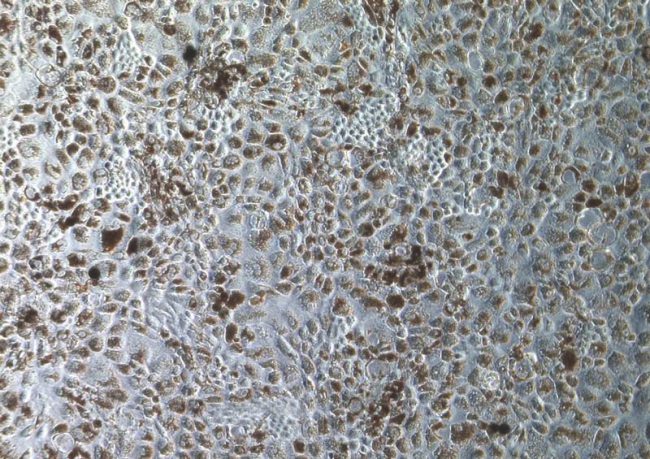

- Retinal Pigment Epithelium (RPE) toxicity assessment

- Retinal Pigment Epithelium (RPE) toxicity assessment